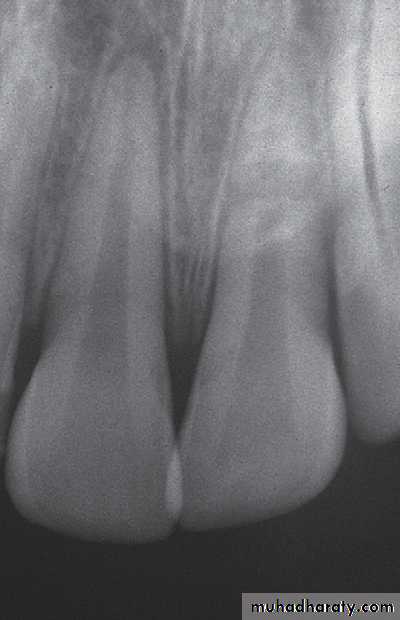

Closed apex maxillary central incisors (mature)Open apex maxillary central incisors (immature)